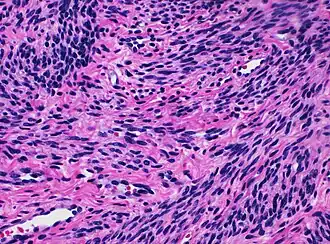

Histology of myometrium

The myometrium is the middle layer of the uterine wall, consisting mainly of uterine smooth muscle cells (also called uterine myocytes[1]) but also of supporting stromal and vascular tissue.[2] Its main function is to induce uterine contractions.

The molecular structure of the smooth muscle of myometrium is very similar to that of smooth muscle in other sites of the body, with myosin and actin being the predominant proteins.[1] In uterine smooth muscle, there is approximately 6-fold more actin than myosin.[1] A shift in the myosin expression of the uterine smooth muscle may be responsible for changes in the directions of uterine contractions during the menstrual cycle.[1]